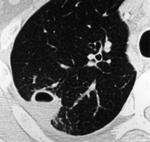

Больной лечился у невролога, провели проф ФГ- выявили деструктивную пневмонию, пролечилили, на Р контроле- ухудшение, клиники абсцесса не было, была боль в гр клетке спереди справа. Из анамнеза- лечился оперативно 6-7 лет назад по поводу рака верхней губы, в ООД не наблюдался последние годы. Данные за туб этиологию сомнительны, как мне кажется, очагов отсева по слоям не вижу,  хотя мож не так смотрю. Ваше мнение коллеги, абсцесс это или нет?

Вполне может быть и полостной формой рака с периканкрозной пневмонией. Пока исследуют мокроту на БК, АК и микрофлору с чувствительностью к антибиотикам, пока лечат, придёт время и для КТ-контроля после лечения. В зависимости от рукастости хирургов, можно было б и пропунктировать - но тут в каждом монастыре свой устав)).

По опыту хочу сказать, что в настоящее время классической клиники абсцесса можете и не увидеть. Очень она изменилась. В данном случае контроль  должен помочь. В связи с тем, что стенки имеют разную толщину и вокруг почти нет изменений, больше склоняюсь к полостной форме рака.